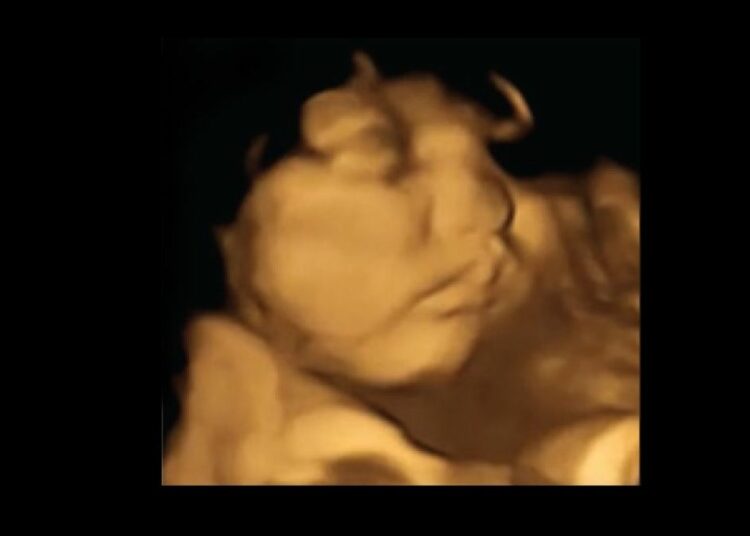

Die Forscher zeichneten mithilfe moderner 4D-Ultraschallaufnahmen die Gesichtsausdrücke ungeborener Kinder in der 32. und 36. Schwangerschaftswoche von 100 Müttern auf. Kurz zuvor hatten die Frauen wahlweise Kapseln mit Karotten- oder Kohlpulver zu sich genommen.

Die Ultraschallbilder belegten: während die Kinder nach der Kohlpulvergabe ähnlich wie beim Weinen das Gesicht verziehen, reagierten sie auf das Karottenpulver mit einem Lächeln. Die Reaktion wird höchstwahrscheinlich durch das Schlucken des Fruchtwassers ausgelöst, welches die Geschmacksstoffe des Pulvers in kürzester Zeit aufnimmt.